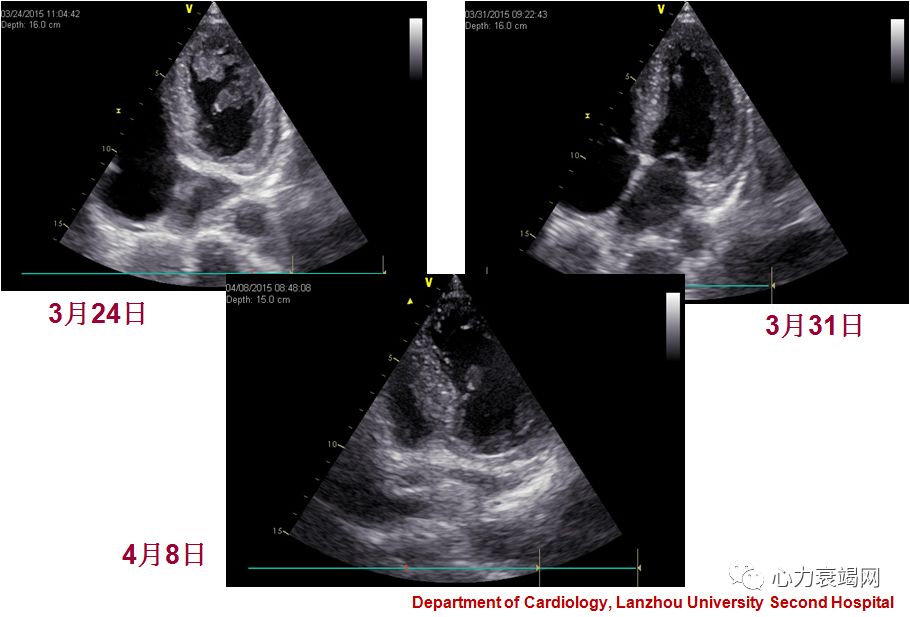

1.应激性心肌病 左室心尖部血栓

应激性心肌病发生时常合并有一过性左室心尖部扩张持续时间?

没有左室一过性扩张的证据